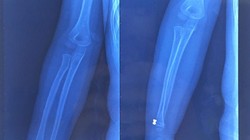

Cùng có bệnh lý về cổ bàn chân như bà M., một bệnh nhân nam 35 tuổi bị đau cổ chân dai dẳng sau chấn thương do chơi đá bóng. Kết quả chụp cộng hưởng từ cho thấy bệnh nhân bịtổn thương viêm xương sụn bóc tách xương sên ở cổ chân - loại tổn thương hiếm gặp. Bệnh nhân đã được phẫu thuật ghép xương sụn nguyên khối (lấy xương sụn từ khớp gối để ghép), điều trị tổn thương. Sau mổ, tình trạng đau của bệnh nhân khi vận động mạnh dần được cải thiện và bệnh nhân có thể trở lại sinh hoạt bình thường sau 3 tháng.